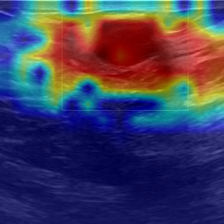

③ Reduced Effective Receptive Field Under Constrained Training Data. To validate whether reduced supervision limits the Adapter’s ability to capture spatially dispersed features and long-range contextual dependencies, we visualize the ERF of Adapters trained on varying proportions of the training set, ranging from 0.63% to 100%, using the COVID dataset and the pretrained ViT-B model. Following the definition in (Araujo et al., 2019), the ERF of a neural network layer refers to the region encompassing all input pixels that exert a non-negligible influence on a given output unit. As shown in Figure 2, the ERF becomes progressively smaller as the amount of training data decreases. This observation supports our hypothesis that limited supervision restricts the Adapter’s ability to learn spatially diverse patterns and long-range contextual relationships, which are particularly crucial in medical imaging tasks. We provide complementary ERF analysis on an alternative backbone (Swin-T) in Appendix F.4, which leads to consistent conclusions, reinforcing the generality of our observations.

To assess whether DKA effectively expands the effective receptive field (ERF), we visualize the ERFs of DKA alongside those of other adapter-tuning baselines, including Adapter (Houlsby et al., 2019), AdapterFormer (Chen et al., 2022), Convpass (Jie et al., 2024), CIAT (Zhu et al., 2021), and AIM (Yang et al., 2023), under both the constrained (0.63%) and the full (100%) training data settings. As shown in Figure 4, DKA consistently exhibits the broadest ERF across both settings, demonstrating its superior ability to capture extensive spatial context even under constrained-data conditions. In contrast, other baselines yield more localized ERFs, particularly in the constrained-data setting, which likely contributes to their comparatively weaker performance.